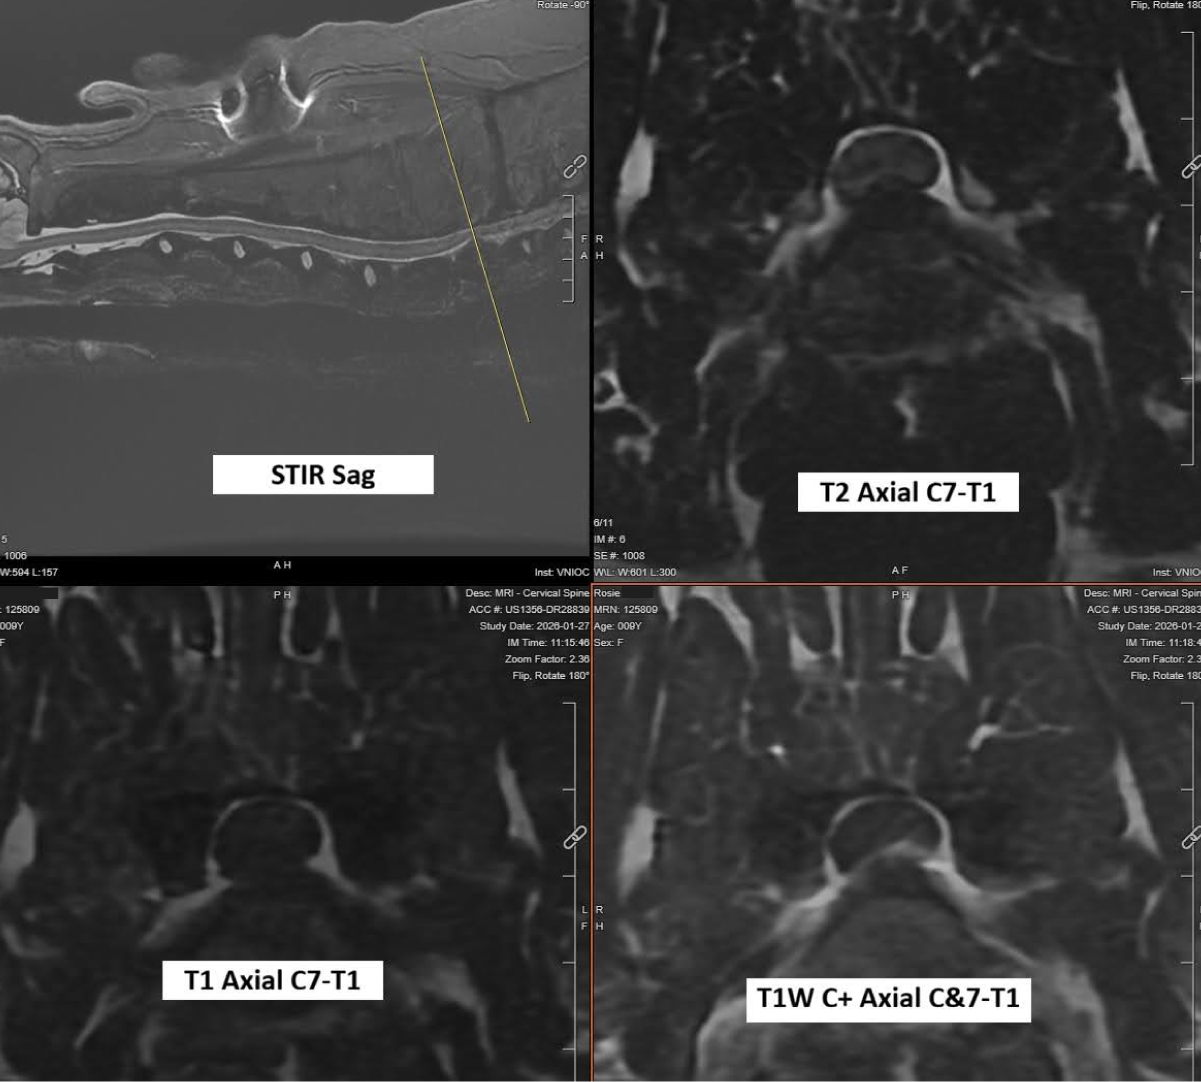

A same-day MRI revealed a chronic disc at C7–T1. Although this is an unusual location, it was presumed to be the cause of Rosie’s neck pain, back pain, and tetraparesis.Rosie’s MRI images demonstrated spinal cord compression from this long-standing disc at the C7–T1 vertebral junction.

Images from Rosie’s MRI: top left is a sagittal (or from the side) image that shows the disk rupture compressing her spinal cord at the level of the line (C7-T1). The other images are cross-sectional images at C7-T1 showing the disk severely compressing her spinal cord.